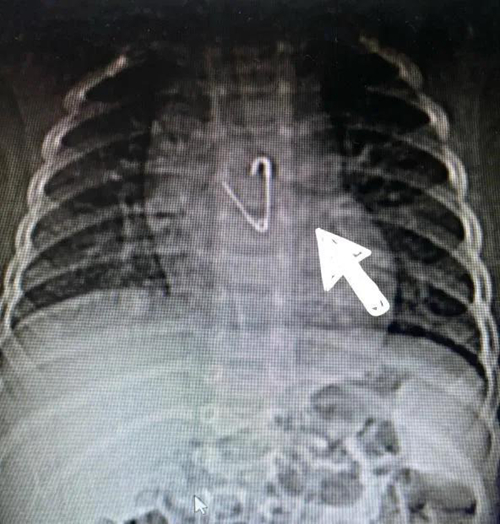

10月4日,剛剛8個月的小鵬鵬(化名)在家玩耍時,不小心吞下一枚別針。心驚膽戰(zhàn)的一家人從平度趕到青島婦兒醫(yī)院就診,接診醫(yī)生迅速為小鵬鵬安排相關(guān)檢查,CT結(jié)果顯示:別針尖端已打開,誤吞的別針?biāo)幬恢梅浅措U,位于食管約胸椎5-7水平處。

由于別針處于張開狀態(tài),可能會隨體位變化而移動,而嬰兒食管管腔狹小,針尖隨時可能劃傷食管造成出血甚至穿孔,引起縱隔及胸腔損傷,導(dǎo)致生命危險。消化科團(tuán)隊立即組織心胸外科進(jìn)行會診,確認(rèn)目前食管沒有穿孔后,專家們決定先用胃鏡探查,如果發(fā)生穿孔等并發(fā)癥,便立即安排手術(shù)治療。

此時正值國慶節(jié)假期,內(nèi)鏡中心主任任悅義和消化科醫(yī)生王瑩瑩第一時間趕到醫(yī)院。根據(jù)X線攝片顯示異物位置及兒童消化道結(jié)構(gòu)特點,消化科和內(nèi)鏡中心團(tuán)隊制定了多種治療方案。在氣管插管全身麻醉后,消化科團(tuán)隊為患兒實施胃鏡檢查。醫(yī)生操作小兒細(xì)胃鏡進(jìn)入食管后,未發(fā)現(xiàn)有異物,繼續(xù)進(jìn)鏡發(fā)現(xiàn)別針已經(jīng)掉入胃內(nèi)幽門口附近,尖端扎入幽門口,萬幸未進(jìn)入腸道,孩子的食管粘膜及胃內(nèi)無明顯損傷及穿孔。根據(jù)術(shù)前制定的預(yù)案,消化科醫(yī)生先用異物鉗把別針“拖”到胃內(nèi),然后加上透明帽,防止損傷胃和食道粘膜,最后通過胃鏡把別針成功取出,手術(shù)過程不到5分鐘,寶寶轉(zhuǎn)危為安。